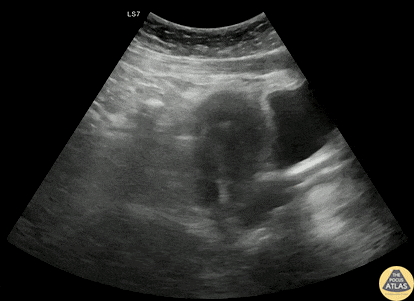

30s F with PMH prior ectopic pregnancy with IUD in place presented with positive home pregnancy test and lower abdominal pain. POCUS demonstrated a visible IUD still in place with free fluid surrounding the uterus. As the patient was hemodynamically stable, she had a consultative TVUS which confirmed these findings. Gynecology took the patient to the OR which confirmed a tubal ectopic pregnancy with a small amount of hemoperitoneum. Dr. Michael MacGillivray, PGY4 Denver Health Residency in Emergency Medicine